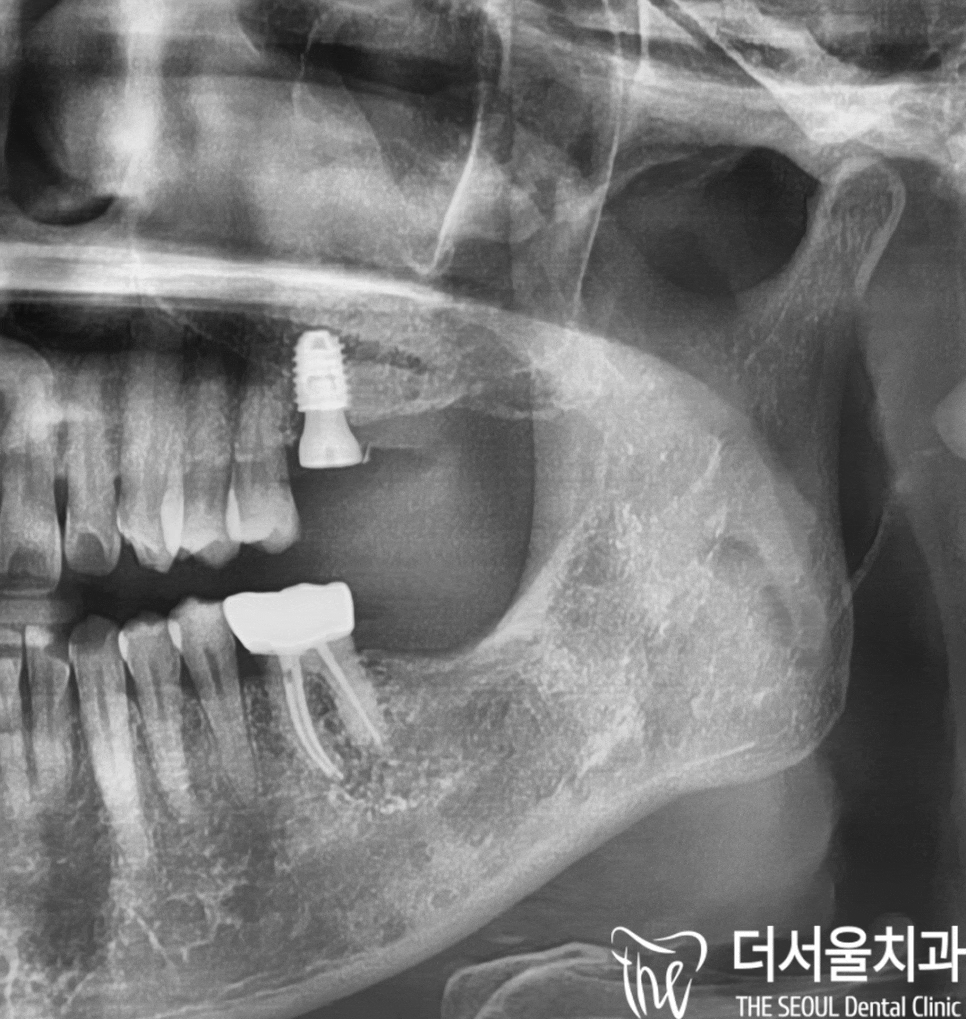

파노라마 사진에서 볼 수 있듯이,

위쪽 어금니->아래쪽 어금니->위쪽 어금니 순으로

차례대로 진행한 것을 알 수 있습니다.

상악동 거상술을 진행했기 때문에

소복한 눈이 내린 것처럼

하얗게 뼈이식재가 비쳐 보이는 것을 볼 수 있으며,

아래쪽에 심었던 것과 다르게

다량의 골 이식재가 진행되었기 때문에

충분한 기간을 두고 지켜보기로 했습니다.

3개월 뒤,

맞춤형 지대주로 기둥을 끼워드리고

지르코니아를 연결해 드리면서

네비게이션 임플란트 수술이 끝나게 되었습니다.

다행히, 상악동 거상술을 할 때도

박리도 잘 되었고

천공 현상도 나타나지 않있습니다.